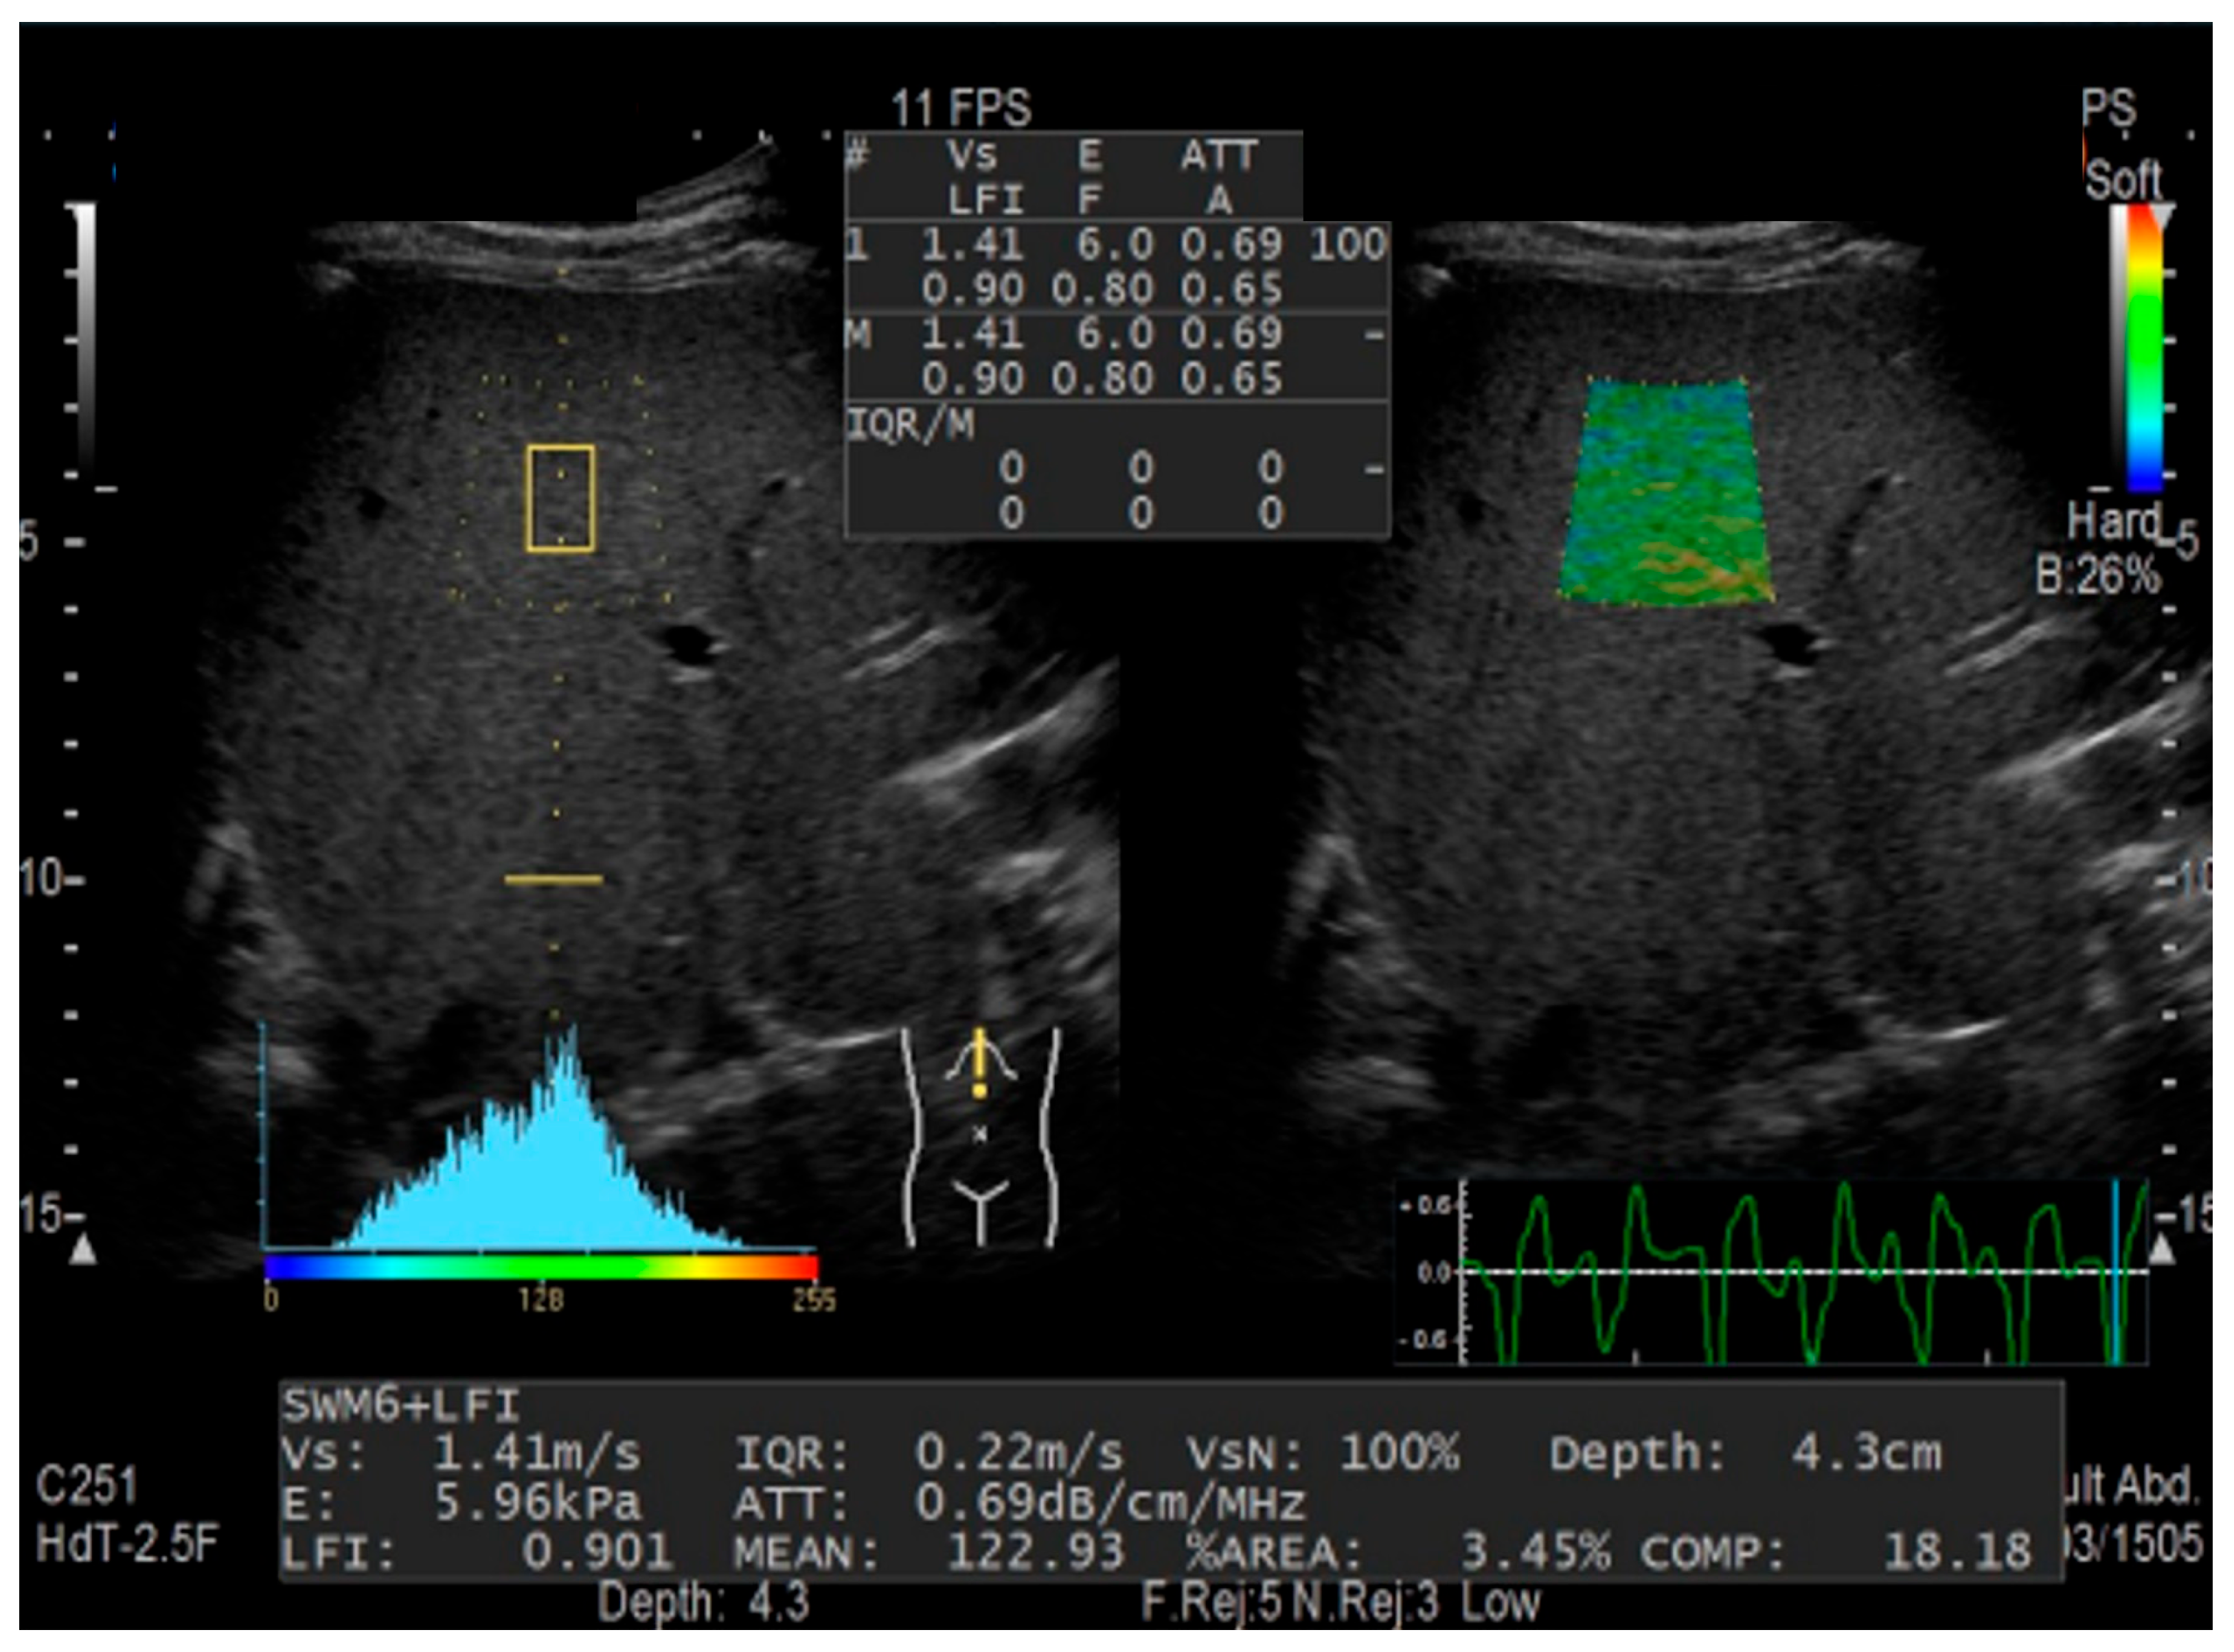

2.2. Combinational Elastography